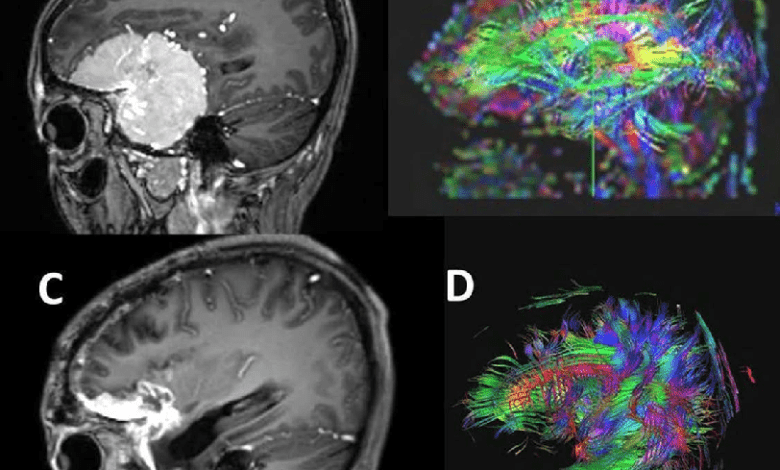

تصویربرداری دیفیوژن تنسور (DTI) یا فن آوری دی تی آی، نوع خاصی از تصویربرداری پزشکی است که به کمک آن مسیر قرار گرفتن رشته های عصبی با رنگهای مختلف در تصویر نشان داده می شود. با استفاده از تصویربرداری دیفیوژن تنسور، در صورت وجود تومور یا توده در مغز، مکان تومور و رشته های عصبی تعیین می شود. بر این اساس جراح می تواند عمل جراحی را به گونه ای برنامه ریزی کند که کمترین آسیب به رشته های عصبی وارد شود. در این مطلب از مرکز تصویربرداری پزشکی تهران۱۰۱ به توضیح روش دی تی آی می پردازیم.

تصویربرداری تانسور انتشار DTI (Diffusion Tensor Imaging) یکی از فناوری های جدید در تصویربرداری پزشکی است. هدف این روش، تهیه یک نمای کلی اساسی و گسترده از مغز است به طوری که درک شهودی کاملی با استفاده از رنگ ها از نقاط قوت و ضعف تصویر ایجاد شود.

پس از تهیه تصاویر اولیه، مدل تانسور قابلیت شبیه سازی اطلاعات سه بعدی فیبرهای عصبی در هر واکسل را فراهم می کند. در نتیجه این فرآیند یک بازسازی سه بعدی (3D) و قابل درک و تفسیر ایجاد می شود.